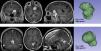

MethodsUnicentric retrospective observational study of a cohort of symptomatic meningiomas surgically removed in the time period between January 2015 and December 2022. Using specific segmentation software, the Surface Factor (SF) was calculated for each meningioma. SF is an objective parameter that compares the surface of a sphere (minimum surface area for a given volume) with the same volume of the tumour against the actual surface of the tumour. This ratio varies from 0 to 1, being 1 the maximum sphericity. Since irregularly-shaped meningiomas present proportionally greater surface area, the SF tends to decrease as irregularity increases. SF was correlated with WHO grade and its predictive power was estimated with ROC curve analysis.

ResultsA total of 176 patients (64.7% females) were included in the study; 120 WHO grade I (71.9%), 43 WHO grade II (25.7%) and 4 WHO grade III (2.4%). A statistically significant difference was found between the mean SF of WHO grade I and WHO grade II–III tumours (0.8651 ± 0.049 versus 0.7081 ± 0.105, p < 0.0001). Globally, the SF correctly classified more than 90% of cases (area under ROC curve 0.940) with 93.3% sensibility and 80.9% specificity. A cutoff value of 0.79 yielded the maximum precision, with positive and negative predictive powers of 82.6% and 92.6%, respectively. Multivariate analysis yielded SF as an independent prognostic factor of WHO grade.

ConclusionThe Surface Factor is an objective and quantitative parameter that helps to identify aggressive meningiomas preoperatively. A cutoff value of 0.79 allowed differentiation between WHO grade I and WHO grade II–III with high precision.